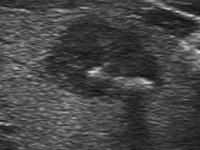

Amyloid deposit

An amyloid deposit has a specific cotton-like patchy appearance (28, 29). We have found this compound figure 118 times more frequently in medullary carcinoma compared with other thyroid malignancies: 48% 11/23 (48%) and 4/463 (0.9%), medullary carcinoma and other thyroid carcinomas, respectively (29). These patches have a composite structure, might contain punctate echogenic foci and occasionally present dorsal acoustic shadow. The cause for the latter might be coarse calcification but a thick amyloid might also hinder the penetration of an ultrasound wave. Similar structures occur even in degenerative hyperplastic nodules when small echonormal areas appear within a hypoechogenic lesion. However, most of the latter, benign cases lack granulations. However, a granulation around a surgical thread might have an identical pattern to amyloid.

There is no general agreement about the origin of this figure. Many authors neglect its typical presentation of this special figure and group them simply among coarse calcifications. E.g., very typical ultrasound images of medullary carcinoma presenting this typical pattern were published in three recent articles and the authors simply notice that the lesion has calcification (Fig.2A in ref. 30, Fig.1 in ref. 31 and Fig.16b in ref 32). I highly advise to review Fig.2A in Trimboli's article (30): the nodule has a large hyperechogenic patch in the central part which lacks dorsal acoustic shadow: it is hard to imagine such a great focus of calcification without acoustic shadowing. The situation is similar in the article of Hoang et al. (32): a typical patch is demonstrated in Fig.16b which lacks dorsal acoustic shadowing.

In my opinion and practice the identification of such compound patches without an acoustic shadow has a high specificity and sensitivity for medullary carcinoma, but if these patches have an acoustic shadow, these parameters are worse though high enough to raise the suspicion of medullary cancer.